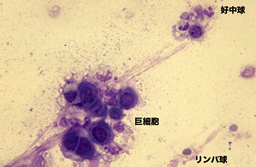

会陰部 男性-男性 感染後3~12日で会陰部や直腸粘膜に5~8mmのびらん・丘疹が発生します。 やがて潰瘍になりますが、痛みがなく数日で治ってしまうので、本人が気づかないことも多いです。 その後1~2週間で、鼠径リンパ節や大腿部リンパ節が腫れます。前立腺の病気には慢性前立腺炎、急性前立腺炎、前立腺肥大症、前立腺癌などがあります。 慢性前立腺炎 あまり知られていない病名ですが、罹患されている男性は多く、すでに治療 中でなかなか良くならず悩んでおられる方も多いと思われます。 命に関 わる病態ではありませんが、ご本人に